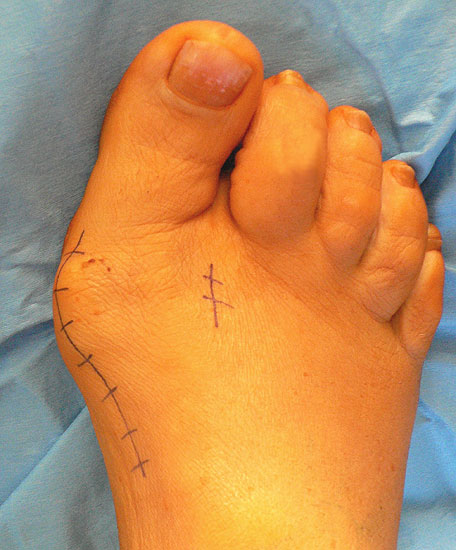

Redressierender Zehenverband

Abbildung 14

• 6 Wochen Verband- oder Vorfußentlastungsschuh. Teilbelastung von 20 kg während der ersten 2 Wochen, dann Vollbelastung. Redressierender Zehenverband (Abb. 14)